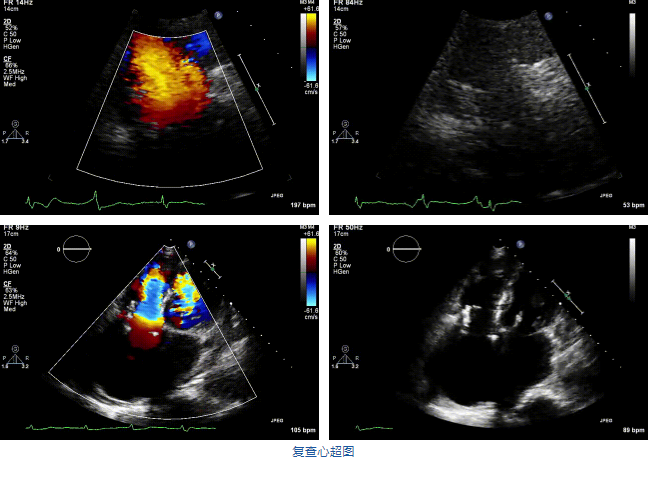

兩例患者是都是外科手術(shù)高危的極重度三尖瓣反流的老年女性,反復(fù)下肢水腫、腹脹、納差,活動耐力減退。一例患者風(fēng)濕性心臟病,二尖瓣生物瓣置換術(shù)后,房顫,心超顯示三尖瓣極重度反流(最大反流寬度15mm);另一例患者房顫,心超示三尖瓣極重度反流(最大反流寬度23mm)。

結(jié)合術(shù)前CT評估結(jié)果,葛均波院士團隊最終決定選用LuX-Valve Plus 50mm和55mm兩種型號的瓣膜,并于2021年11月30日順利完成LuX-Valve Plus經(jīng)血管三尖瓣置換術(shù),手術(shù)室即刻拔除氣管插管,術(shù)后第二天轉(zhuǎn)出心內(nèi)科監(jiān)護室,下床活動。術(shù)后患者三尖瓣反流癥狀得到顯著改善,復(fù)查心超結(jié)果顯示人工三尖瓣瓣膜支架固定穩(wěn)定,瓣葉關(guān)閉形態(tài)未見異常,未見明顯反流。